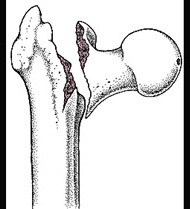

股骨转子间骨折(如图)容易发生的并发症是()

A.骨折不愈合

B.损伤性骨化

C.髋内翻畸形

D.创伤性髋关节炎

E.股骨头缺血性坏死